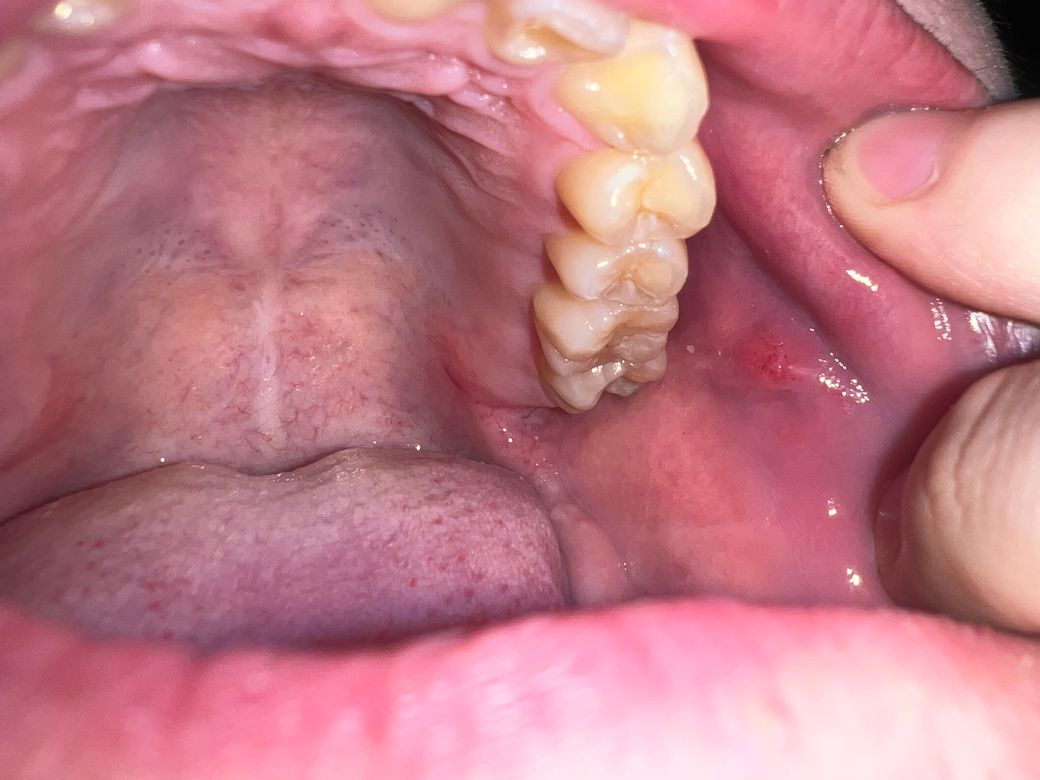

오늘 밥을 먹다가 볼 점막에 혹 처럼 만져지는 게 있어서 사진을 찍었습니다. 사진에서는 잘 안 보이지만 원래 점막을 찢고 나온 거 처럼 아래에 하얀 점막이 보이고 툭 올라온 것에는 붉고 작은 반점이 보입니다 그리고 혀로 건드려도 아프지 않고 딱딱한 게 느껴집니다

Stensen duct로 보여집니다.

걱정은 안하셔도 되겠고 침이 나오는 곳이라고 생각하시면 되겠습니다.

사진상 구내염으로 보이며, 충분한 휴식과 영양섭취를 권합니다. 염증이 덧나지 않도록 소독용 가글인 헥사메딘 가글액으로 가글을 하여 관리하고, 만약 2주이상 사라지지 않는 경우에는 치과 진료를 권합니다.